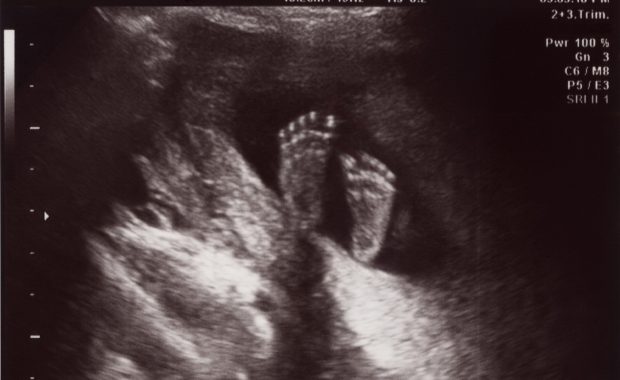

O veste excelentă: refuzul medicilor români de a efectua avorturi se extinde

Utilizarea excesivă a cezarienelor afectează fertilitatea în Coreea – și în întreaga lume

În Coreea, un procent incredibil, de 59%, din nașteri au loc prin cezariană. Aceasta este una dintre Citește...